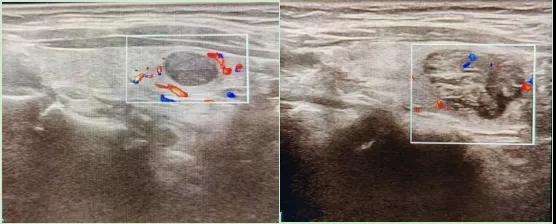

二、彩超如何“揪出”甲狀腺瘤?

彩超是一種無(wú)創(chuàng)、無(wú)輻射的檢查手段,被譽(yù)為甲狀腺的“高清攝像頭”。它的原理是:

超聲波探測(cè):通過(guò)發(fā)射高頻聲波,生成甲狀腺的實(shí)時(shí)圖像。

彩色血流顯示:用紅藍(lán)色標(biāo)記血流信號(hào),區(qū)分腫瘤的供血情況。

醫(yī)生會(huì)通過(guò)以下特征判斷腫瘤性質(zhì):

1.形態(tài):良性多呈圓形,邊界清晰;惡性可能不規(guī)則、邊緣模糊。

2.回聲:低回聲結(jié)節(jié)風(fēng)險(xiǎn)較高(像“烏云”一樣暗)。

3.鈣化:細(xì)小砂礫樣鈣化提示惡性可能。

4.血流信號(hào):惡性結(jié)節(jié)常有豐富紊亂的血流。